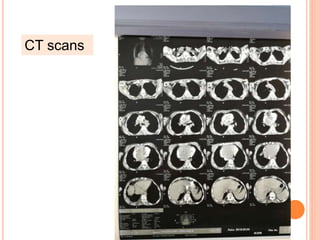

CT scans

 CT